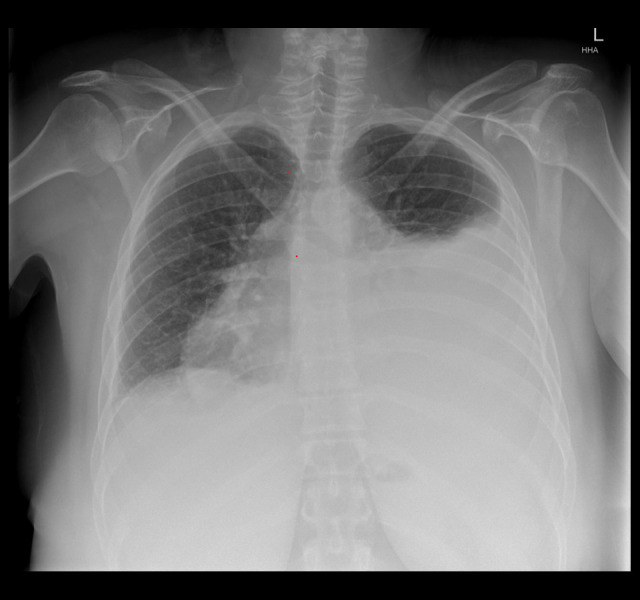

心包炎是系统性红斑狼疮(SLE)的常见并发症。然而,大量心包积液引起的心包填塞是一种罕见的后遗症。SLE患者发生心包填塞的危险因素包括女性、血清补体降低和诊断时抗核小体抗体阳性。心包填塞的治疗方案,如心包穿刺和心包开窗,都是针对个体量身定制的,并且缺乏关于何时进行侵入性干预的明确指南。病例报告:我们报告一例38岁女性SLE加重合并心包填塞,伴有发热、呼吸困难和胸膜炎性胸痛。胸片显示大量左侧胸腔积液掩盖了增宽的纵隔,怀疑为心包积液。在药物治疗试验后,患者出现了新的心房颤动、低血压和心动过速,并进行了心包穿刺,随后在接下来的24小时内抽出了1.6升心包液。采用高剂量脉冲皮质类固醇和环磷酰胺治疗,疾病得到控制,积液无复发。结论:这似乎是文献中描述的SLE患者心包引流量最大的一例。心包填塞可发生在SLE病程的任何阶段。大量胸腔积液可模仿心包积液的症状,使诊断具有挑战性。采用侵入性和药物治疗相结合的方法可以达到最终的治疗效果。心包填塞发生的危险因素应在SLE恶化的早期识别,以确保及时治疗并避免进一步的并发症。

BACKGROUND Pericarditis is a frequently encountered complication of systemic lupus erythematosus (SLE). However, cardiac tamponade resulting from massive pericardial effusion is a rare sequela. Risk factors for cardiac tamponade in SLE include female sex, reduced serum complement, and positive anti-nucleosome antibody at diagnosis. Management options for cardiac tamponade, such as pericardiocentesis and pericardial window, are tailored to the individual, and clear guidelines for when to proceed with invasive intervention are lacking. CASE REPORT We present a case of cardiac tamponade associated with an SLE exacerbation in a 38-year-old woman, associated with fever, dyspnea, and pleuritic chest pain. A chest radiograph demonstrated a large left pleural effusion obscuring a widened mediastinum suspicious for pericardial effusion. After a trial of medical therapy, the patient developed new atrial fibrillation, hypotension, and tachycardia, and proceeded to pericardiocentesis following which 1.6 liters of pericardial fluid was drained over the following 24 hours. Disease control was achieved with high-dose pulsed corticosteroids and cyclophosphamide and there was no recurrence of the effusion. CONCLUSIONS This appears to be one of the largest volumes of pericardial drainage described in the literature in the setting of SLE. Cardiac tamponade can occur at any stage of the disease course in SLE. Large pleural effusions can mimic symptoms of pericardial effusion and make diagnosis challenging. Definitive management can be achieved using a combination of invasive and medical therapy. Risk factors for the development of cardiac tamponade should be identified early in the course of an SLE exacerbation to ensure prompt treatment and avoid further complications.